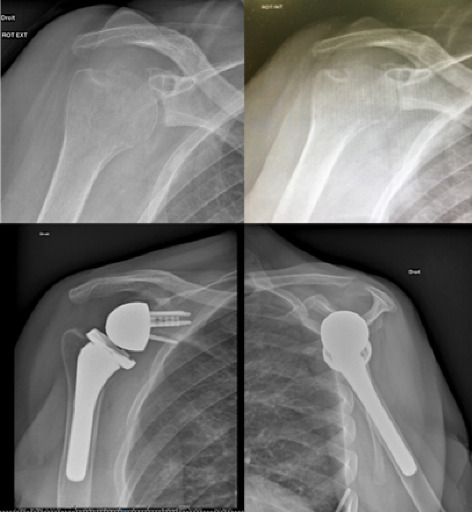

We report a rare case of reverse shoulder prosthesis implantation in a patient retrospectively showing a chronic tuberculous osteoarthritis and meningitis. In this atypical presentation, the patient presented only a chronic shoulder pain, with no clinical or imaging sign of tuberculosis. After the implantation of a reverse shoulder prosthesis, the patient presented a reactivation of a tuberculosis causing a meningitis. The diagnosis of shoulder osteoarthritis caused by M. tuberculosis was confirmed retrospectively on deep perioperative samples by standard culture, PCR, and positive pathology. The management of the patient consisted in 12 months of a medical antituberculosis therapy and showed a favorable outcome.